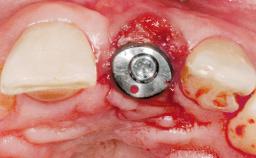

Immediate Placement of an Implant in a Maxillary Left Central Incisor Site

Type of Implants One-Piece

Attachment One-Piece

Placement Protocol Immediate implant placement

Tooth Site Maxillary incisor or canine

Socket Morphology Single-root socket